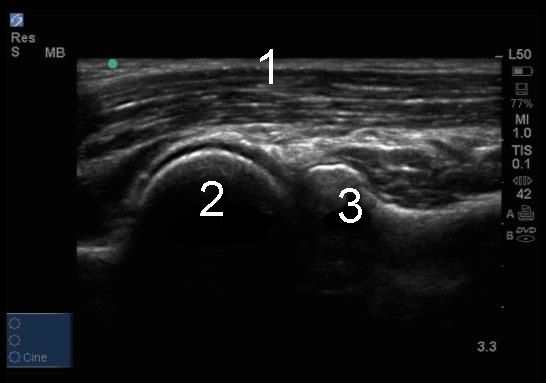

Elbow Lateral Radiocapitellar Joint Image

Brachialis Muscle

Lateral Epicondyle

Radial Head